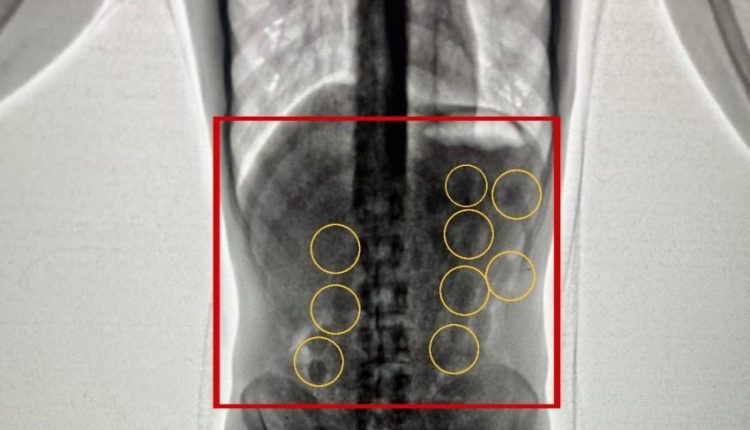

وبعد تفتيشهما والكشف عليهما بواسطة الاجهزة اللازمة اكتُشف وجود كميات من المواد المخدرة داخل أحشائهما ، وجرى إخراج هذه المواد بالطرق الطبية، وقُدرت ب 2 كغم من مادة الكوكايين المخدرة .